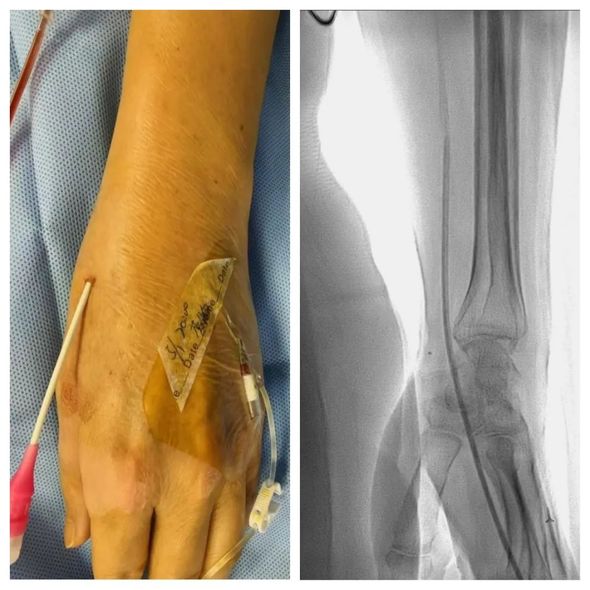

手术选取远桡动脉入路

术中部分图像